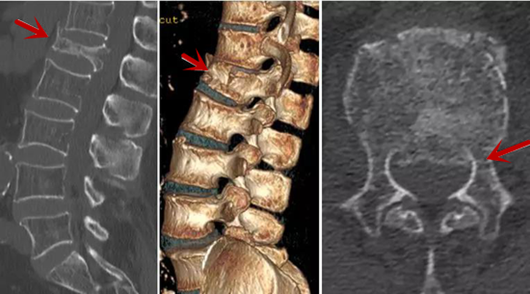

CT利用X射線對人體檢查部位通過電腦切成若干層掃描,然后把每層的圖像都能顯示出來。CT相對于X光片具有更高的密度分辨力,可直接顯示X線片無法顯示的病變,觀察腰椎有無微小的骨折、骨質有無破壞等骨質情況、以及腰椎間盤突出、腰椎神經根、椎管、椎間小關節的情況等。同時還可以通過后處理,重建腰椎矢狀位或冠狀位圖像,形成腰椎的3D圖像,更直觀地觀察病變部位,對腰椎手術風險具有提示作用,對手術方式的選擇具有指導意義,但是對神經、脊髓損傷程度的顯示不如MRI,軟組織的分辨率仍有一定限制,對椎管內病變顯示欠佳,且有一定的輻射。

箭頭提示椎間盤突出

從左向右依次為CT矢狀位重建圖像、三維重建圖像、軸位掃描圖像,箭頭提示腰1椎體爆裂性骨折